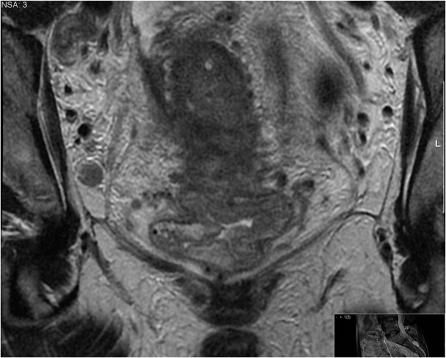

基于表格的直肠癌报告。

Proforma-based reporting in rectal cancer.

The improvements in outcomes associate with the use of preoperative therapy rather than postoperative treatment means that clinical teams are increasingly reliant on imaging to identify high-risk features of disease to determine treatment plans. For many solid tumours, including rectal cancer, validated techniques have emerged in identifying prognostic factors pre-operatively. In the MERCURY study, a standardised scanning technique and the use of reporting proformas enabled consistently accurate assessment and documentation of the prognostic factors. This is now an essential tool to enable our clinical colleagues to make treatment decisions. In this review, we describe the proforma-based reporting tool that enables a systematic approach to the interpretation of the magnetic resonance images, thereby enabling all the clinically relevant features to be adequately assessed.

摘要

术前治疗而非术后治疗带来的结果改善意味着临床团队越来越依赖于影像学来识别疾病的高危特征以确定治疗方案。对于许多实体瘤,包括直肠癌,已经出现了用于术前识别预后因素的验证技术。在 MERCURY 研究中,标准化的扫描技术和报告表格的使用使得对预后因素的准确评估和记录成为可能。这现在是我们的临床同事做出治疗决策的重要工具。在这篇综述中,我们描述了基于报告表格的报告工具,它使我们能够对磁共振图像进行系统的解读,从而能够充分评估所有与临床相关的特征。